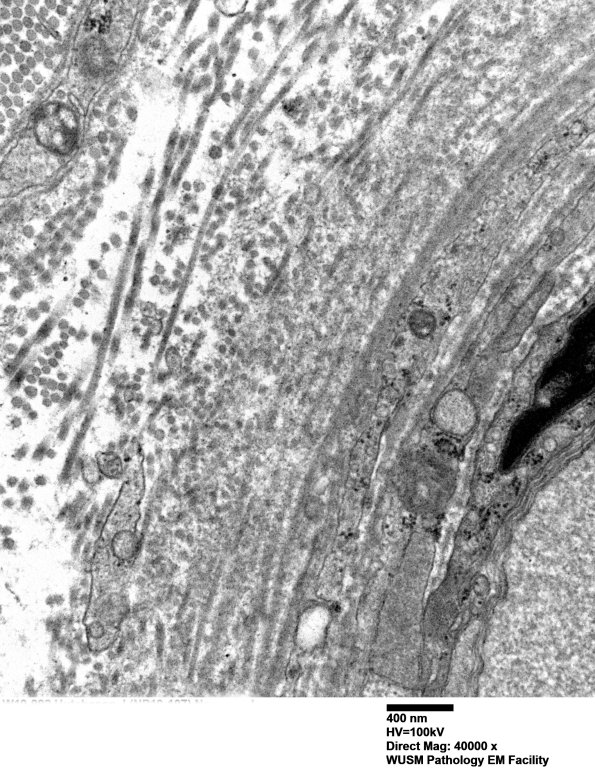

Washington University Experience | VASCULAR | Hypoxia-Ischemia, fetal-neonatal | White Matter | 14B2D (Case 14) EM014 - Copy

14B2D (Case 14) EM014 - Copy